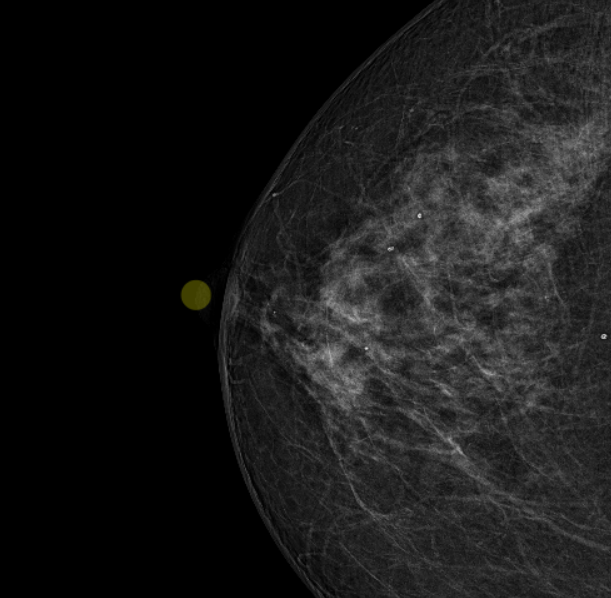

- Podpora rotace HP v případě více nastavených Hanging Protokolů, např. běžně u mamografických snímků, je nyní možné procházet předvolené HP ve smyčce v rámci skupiny HP bez přepnutí na další skupinu HP, popřípadě takto procházet skupiny HP při použití nástroje „Přepnout na následující HP/fázi HP“, či klávesové zkratky. Tuto funkci naleznete v pravé postranní liště „Pracovní sady nástrojů zobrazení“.